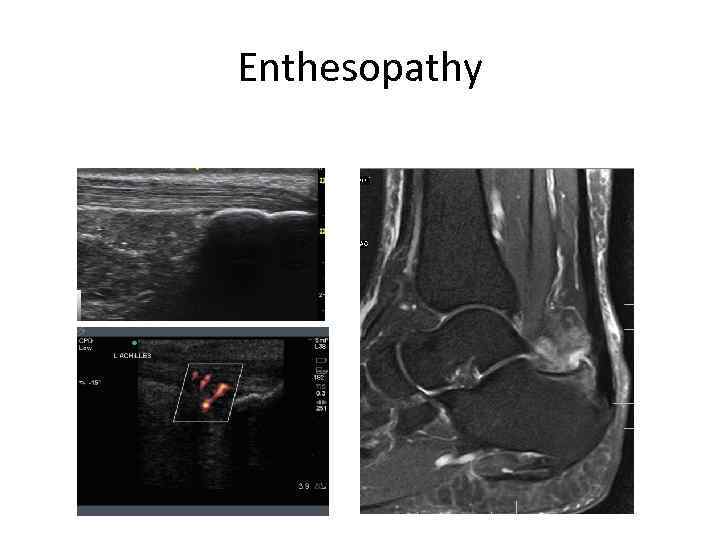

Enthesopathy

Enthesopathy

Enthesopathy